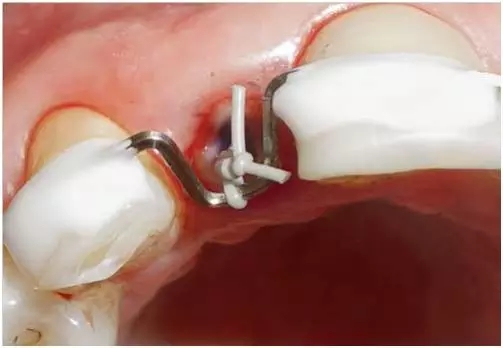

為了重新恢復牙齒的形態(tài),需要一個根管樁以便更好地固位冠結構,但之前必須將原來的已折斷的鈦樁去除。在牽引牙根之前去除斷樁,可以判斷是否發(fā)生根縱折,確定牙根是否具有繼續(xù)保留的價值。另外,冠方根管部分用于固位牽引環(huán)。由于牙齒的根部結構細,所以應該避免過度地使用超聲工具和去除過多的牙體硬組織。因此,在去除斷樁(大約6mm鈦樁)時建議在放大術野和光照(例如:牙科手術顯微鏡或者放大鏡并配有直接的光源)下進行,并使用金剛砂鉆或者碳化鎢鋼鉆在保護牙體硬組織的前提下去除(圖8至10個)。根尖三分之一的牙膠保留至牽引結束,如必要則重新充填,并且操作在使用橡皮障充分隔濕后(牽引后)進行。用一層Cavit覆蓋牙膠,以確保輕松進入根管的根尖部位(圖11)。之后,以酸蝕粘接技術用牙本質粘合劑和Permaflow purple 將牽引環(huán)聚合固定在冠方的牙根部分。將一個穩(wěn)定的方弓絲貼合并固定于兩側各兩顆鄰牙上,以實現(xiàn)根的軸向牽引。固定在根管內(nèi)的牽引環(huán)通過連接在方弓絲上的彈性絞合絲加力(圖12至圖15)。然后將牙周纖維切斷,以防止骨和軟組織“共同”冠向位移。正畸加力可以每周通過更換新的彈性絞合絲來實現(xiàn),同時在就診時也要將牙周纖維切斷。在大多數(shù)病例中,大約經(jīng)過6至12 周之后都能達到足夠的牽引距離,之后需要至少保持6周并且可能要做必要的牙周外科手術(去骨和牙齦成形)。

圖8:在放置牙齦收縮線和橡皮障隔離12牙后的臨床檢查:采用聯(lián)孔技術放置橡皮障。用Permaflow purple 封閉橡皮障周圍并暫時固定于鄰牙。在口腔顯微鏡下用金剛砂鉆去除鈦根樁。

圖12:12牙的臨床檢查:采用酸蝕粘接技術, 用牙本質粘合劑和Permaflow purple 在根管冠方段固定牽引環(huán)后的情況。

圖13:12牙的臨床檢查:開始正畸牽引牙根。牽引環(huán)被用彈性絞合絲固定在方弓絲上。

圖14:12牙的臨床檢查:正畸牽引牙根。方弓絲定位的原則是牙根要能在根軸向被牽引出